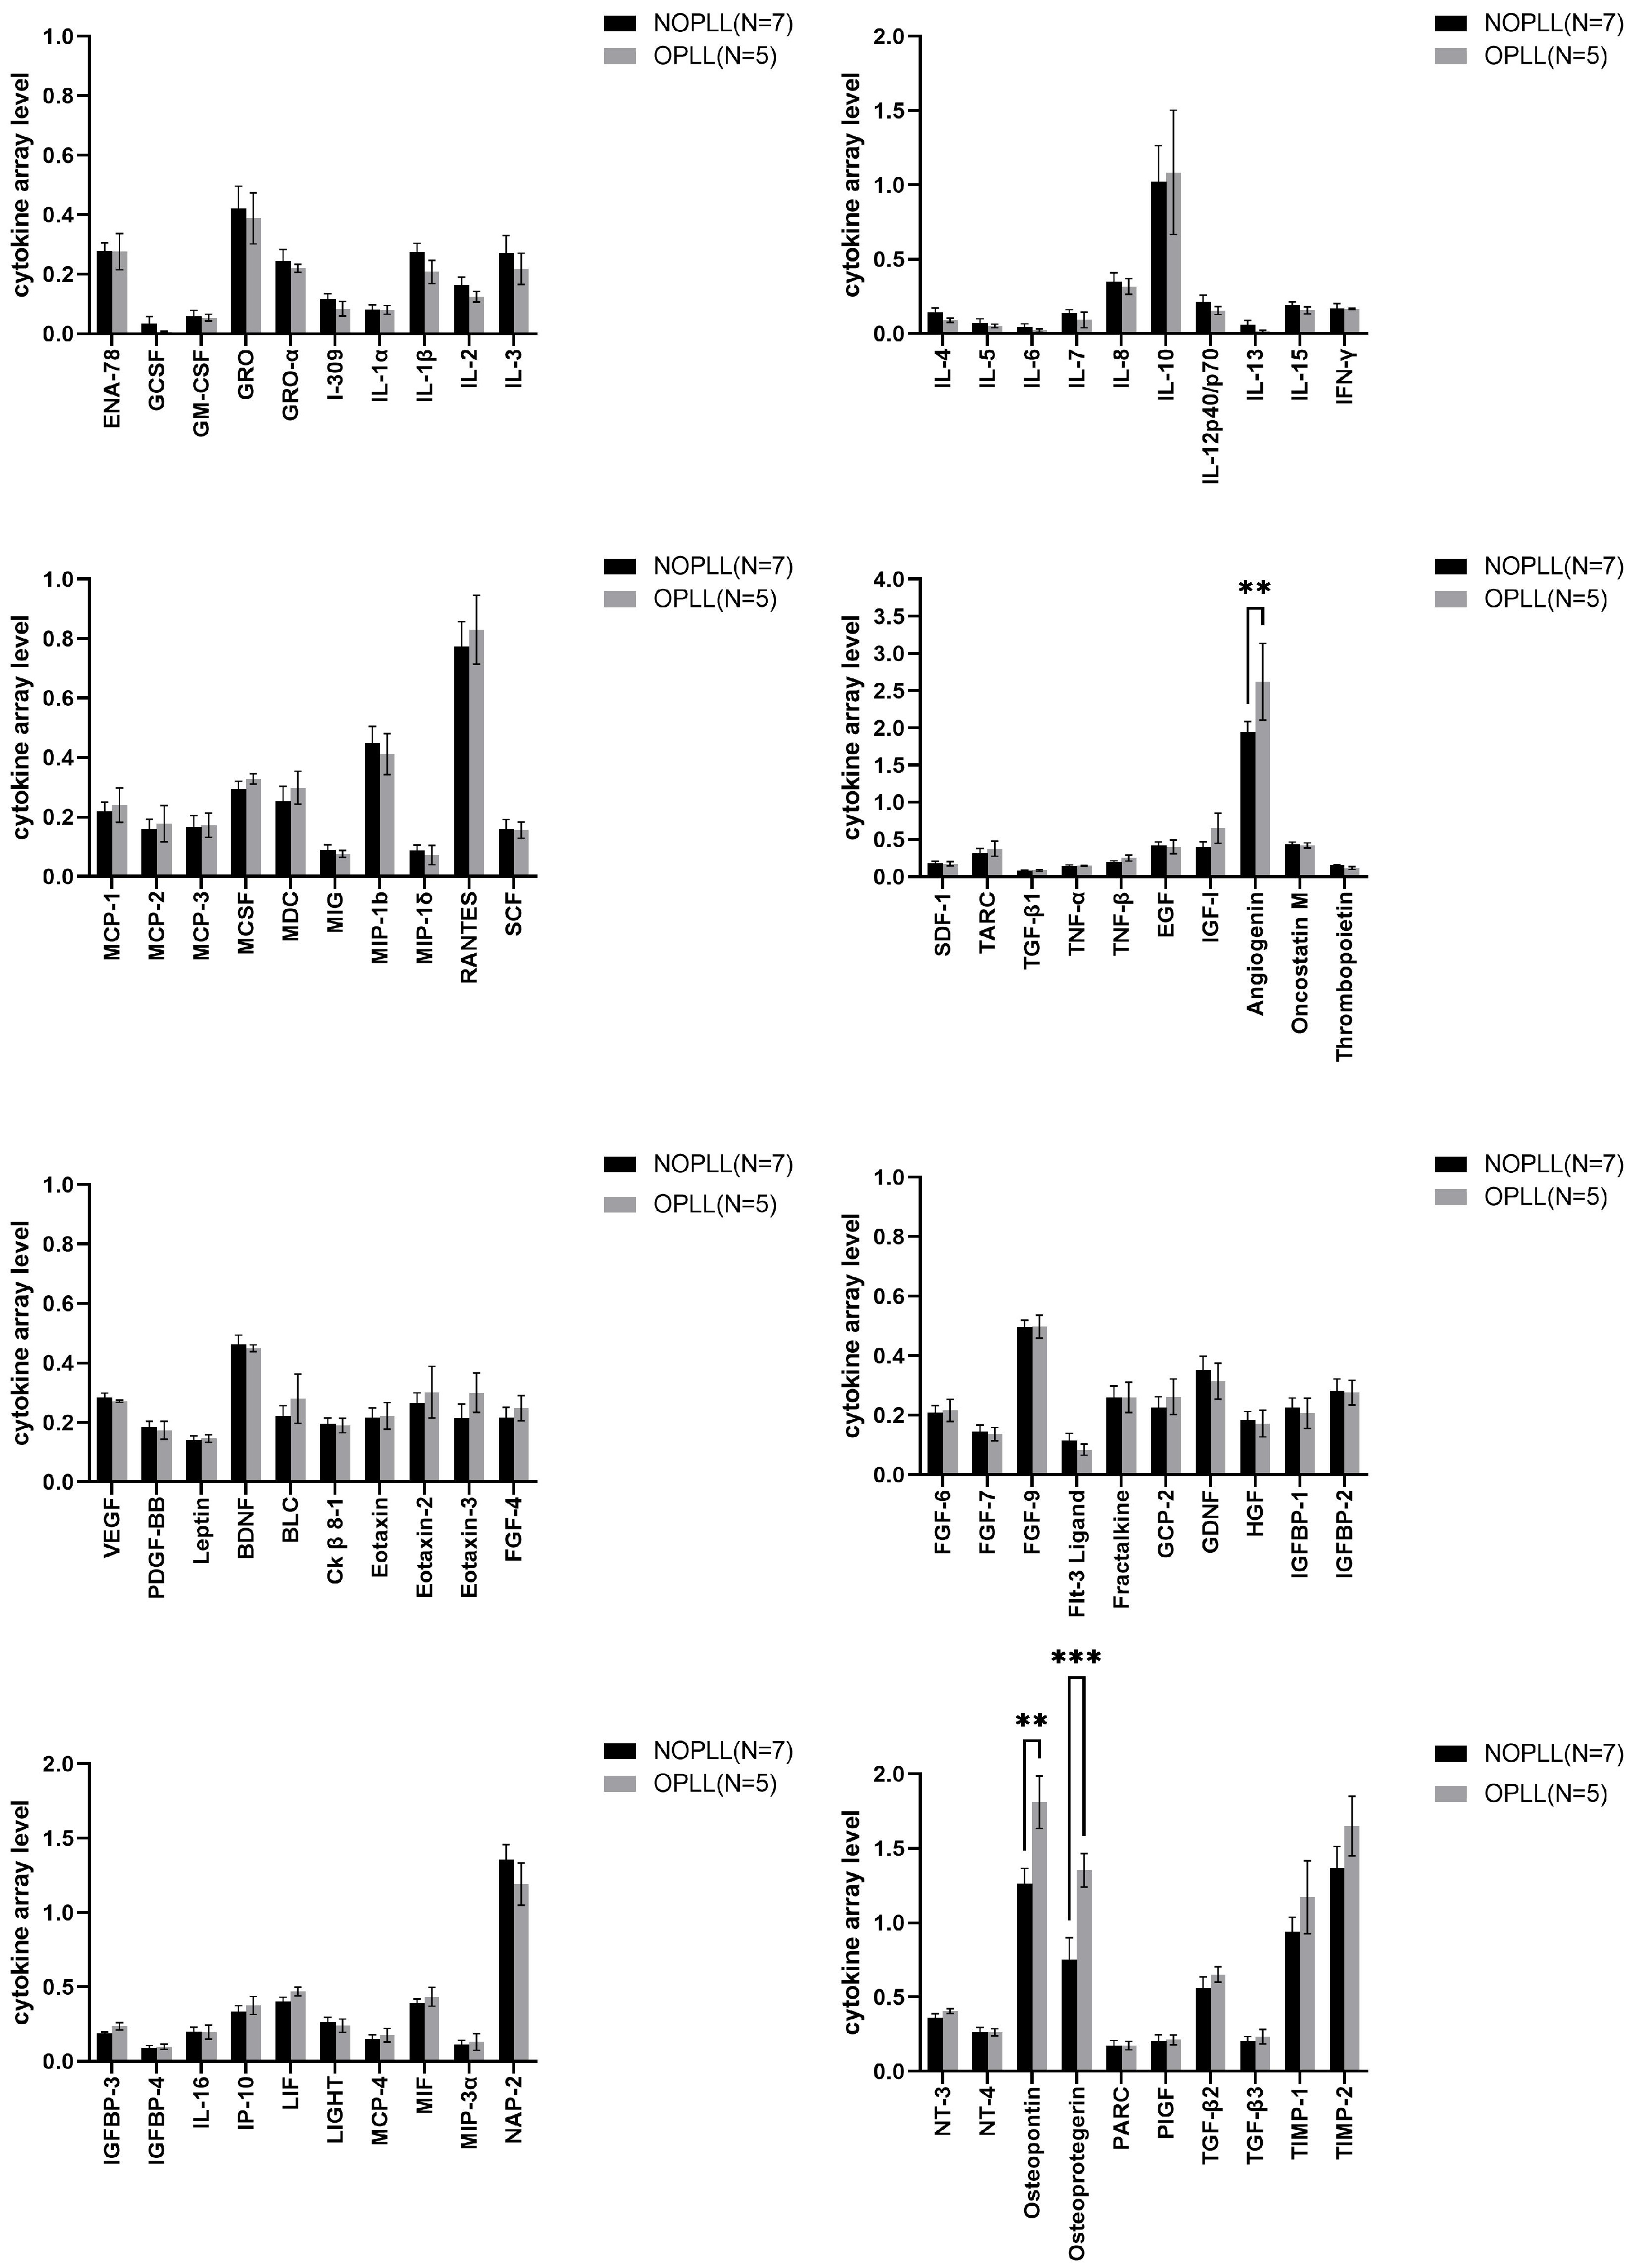

3.4. Tissue Cytokine

3.5. Level of Proteins in OPLL vs. NOPLL

3.6. Levels of Proteins in Serum vs. Tissue: Serum/Tissue > 2

3.7. Levels of Proteins in Serum vs. Tissue: Tissue/Serum > 2

4.4. Angiogenesis Factors: ANG, vEGF, and Osteopretegerin

4.8. Osteopontin (OPN)

4.9. Osteoprotegerin OPG